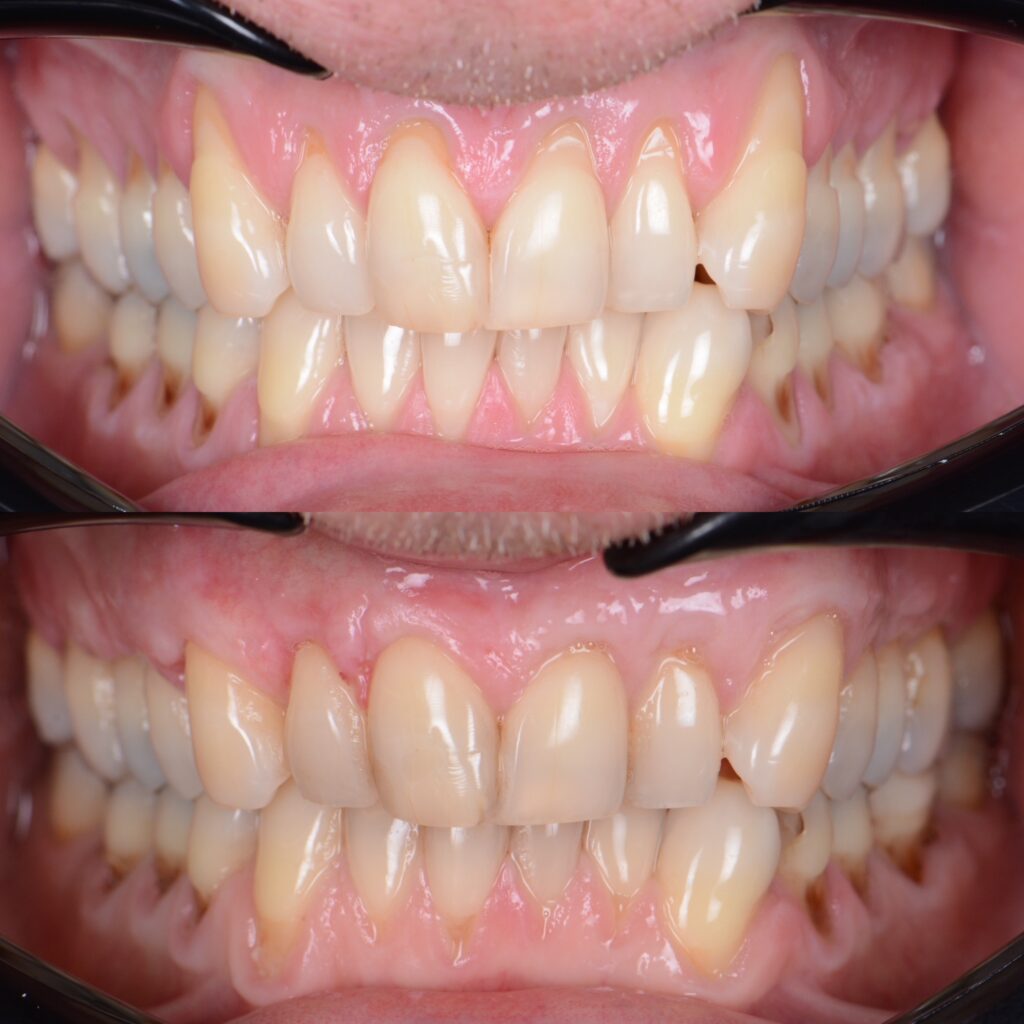

Sie finden einige Vorher/Nachher Fotos sowie Behandlungsbeispiele von Patienten die Dr. Azzawis Praxis wegen Zahnfleischrückgang aufgesucht haben.

Klinische Fälle

Case 14